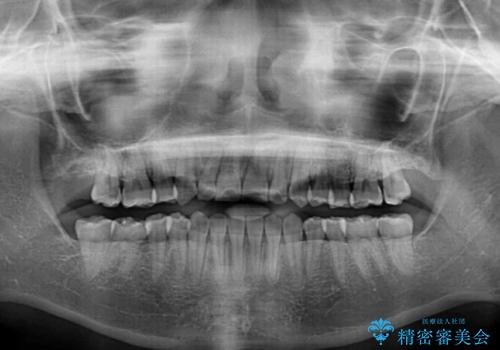

- 前歯のデコボコや八重歯、舌癖による開咬を気にして来院された患者様です。

目立たない装置を希望されたので、上顎が裏側装置のハーフリンガルを選択し、上顎小臼歯1本を抜歯して、補助装置を併用して矯正治療を行うこととしました。

補助装置を事前に使用したことで、あっという間に八重歯が改善し、ハーフリンガルにしては1年半もかからずに治療を終えることができました。